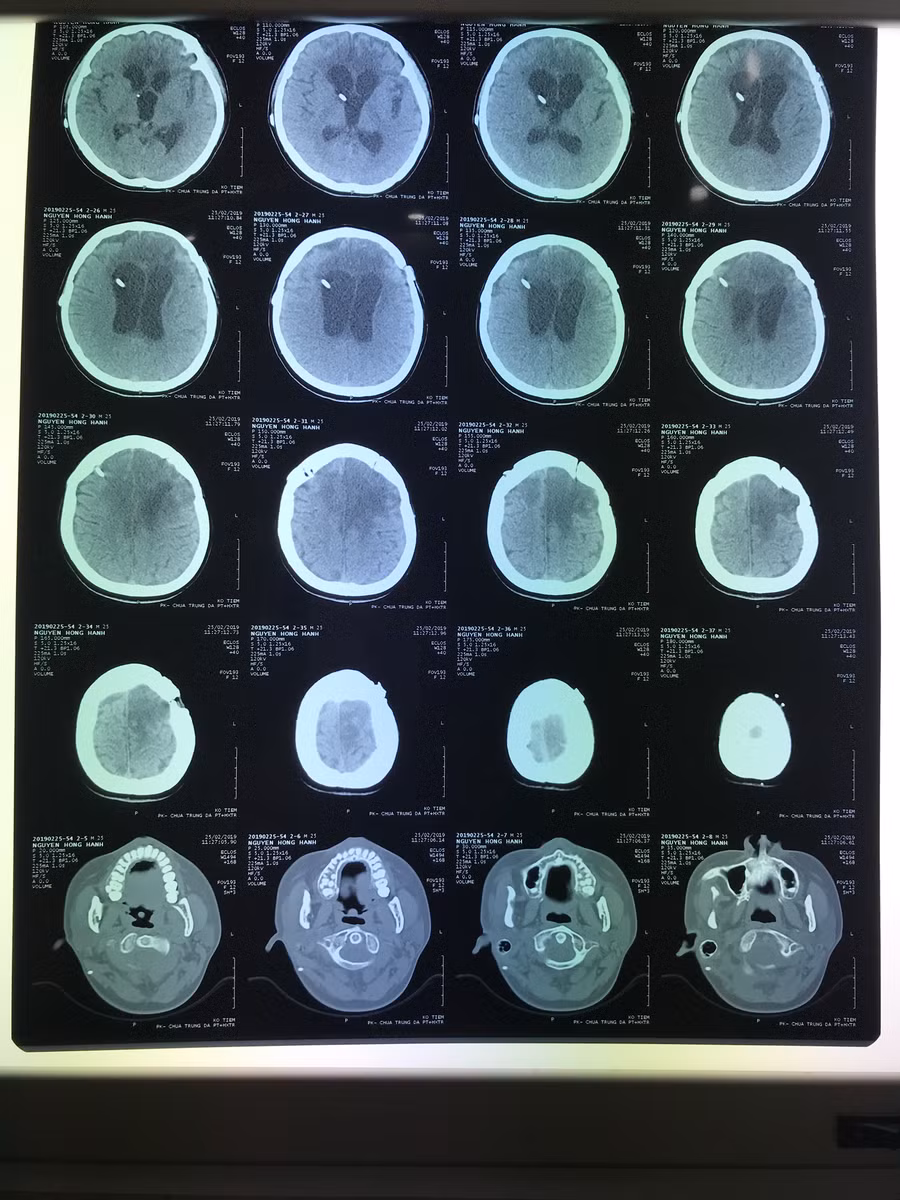

| Phim chụp tình trạng bệnh nhân bước đầu ổn định |

Người nhà bệnh nhân cho biết H. được chẩn đoán xuất huyết não, đã cắt u não vi phẫu, dẫn lưu não thất ra ngoài. H. nhập viện trong tình trạng hôn mê sâu, không ý thức, chỉ số HCG 276.28 mUI/ml; kết quả giải phẫu bệnh ChorioCarcinoma. Các bác sĩ chẩn đoán bệnh nhân H. ung thư buồng trứng di căn não. Sau khi điều trị hồi sức nội khoa, xạ trị toàn não 20Gy kết hợp truyền hóa chất Methotrexate 6 đợt và phẫu thuật dẫn lưu não thất - ổ bụng thì đến tháng 11/2018 bệnh nhân có dấu hiệu sinh tồn ổn định, nhận thức được người thân.